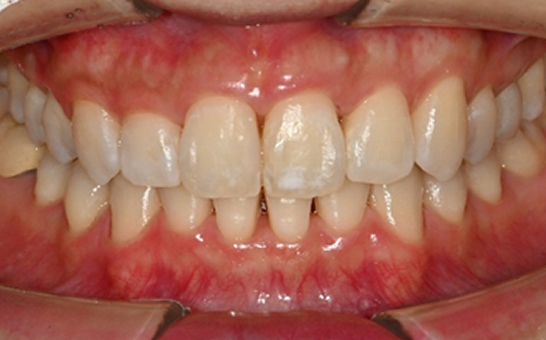

※ 바른선택치과의원은 의료법을 준수하며 위 케이스는 실제 내원 환자분의 동의하에 공개된 사진과 동일한 환자분께 같은 조건에서 촬영한 사진을 활용했습니다.

개인에 따라 진료 및 치료 방법이 다르게 적용할 수 있으며, 효과와 부작용이 개인마다 다르게 나타날 수 있는 점을 안내해 드리며, 진료 전 전문의료진과 충분한 상담을 권해드립니다.